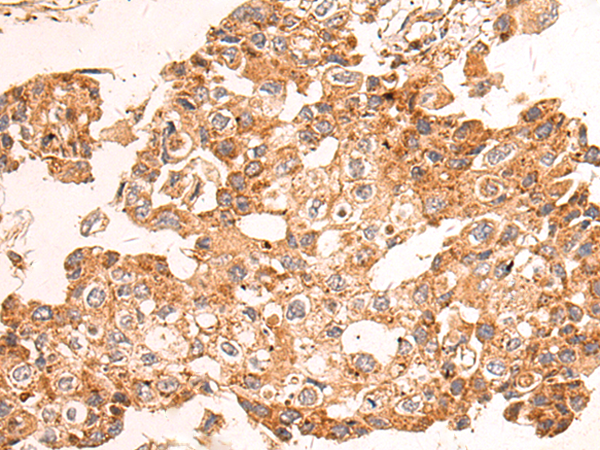

分类: 科研抗体货号: P01604别名: CN1; CNI; CN-I; CN1A; CN-IA应用: IHC反应种属: Human, Mouse